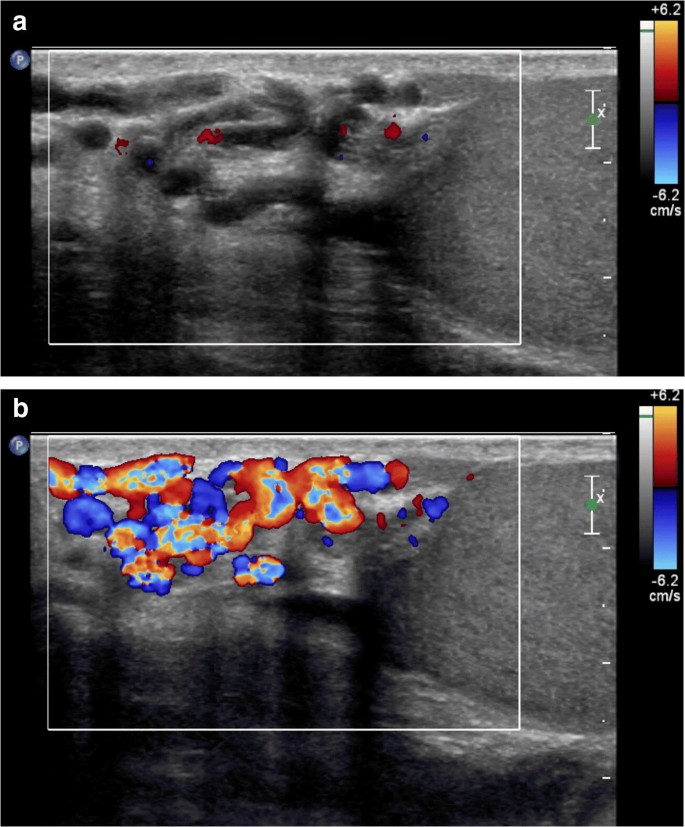

Varicocele bilateral com refluxo ao doppler. Portanto a varicocele é uma insuficiência na drenagem de sangue do testículo que leva ao represamento sanguíneo e ao aumento do volume das veias. Como já foi dito é nada mais do que uma variz. Acontece quando existem pequenas alterações que não são visíveis e nem palpáveis quando o paciente encontra se de pé. Eco doppler colorido é um método muitas vezes empregado para confirmação diagnóstica de varicocele.

Na cirurgia fecham se as veias do plexo venoso testicular curando a varicocele. Grau i varicocele pequena sendo palpável apenas com aumento da pressão abdominal. A partir do grau de desenvolvimento de cada caso o médico poderá classificar a varicocele de 3 formas. Currently in the ultrasound study of varicocele the diameter of the veins is carried through with the patient in the supine position before and during the valsalva maneuver taking the diameter of the veins consideration 0 20cm and a more than 1 second bigger presence of reflux according to spectral doppler study.